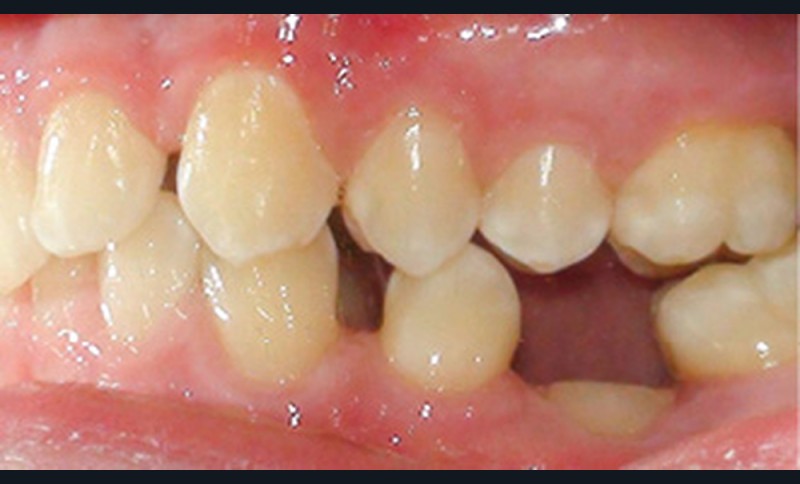

L’infraclusion de la molaire temporaire, et dans son cas extrême sa réinclusion, est le résultat d’une ankylose de la dent. Cette dent ne pourra plus suivre la croissance de l’os maxillaire ou mandibulaire et ainsi le plan d’occlusion. La molaire temporaire ne présentant pas de germe définitif sous-jacent, elle s’ankylose fréquemment à un stade plus ou moins avancé de l’individu et de la croissance des maxillaires.

D’un point de vue histologique, dans l’ankylose dento-alvéolaire, il existe une continuité de tissus durs (os-cément) avec rupture du ligament alvéolo-dentaire, précédée par une disparition locale des éléments épithéliaux de Malassez, isolants de la gaine péri-dentaire [1]. Il en résulte une résorption de la racine dont la vitesse correspond à la vitesse du remodelage osseux. Ce processus est défini comme « résorption de remplacement », l’os prenant la place du desmodonte et de la racine dans la zone ankylosée [2]. Lorsque…